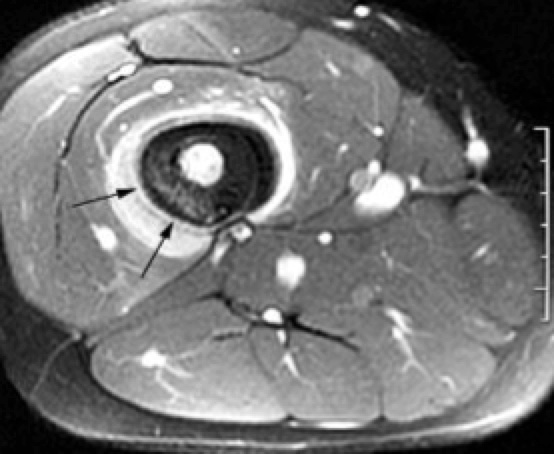

Axial image shows bright enhancing sarcoma